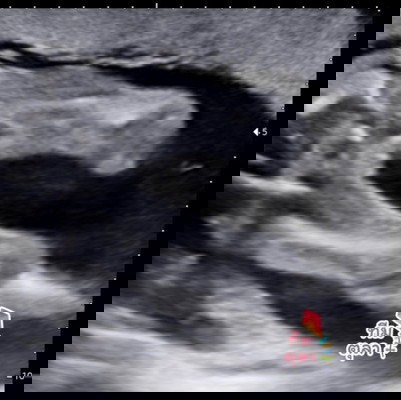

19 week 3 day ลูกสาวชัวๆใช่ไหมคะ ทีมตุลาค่ะ #ท้อง2 ท้องแรกได้น้องผู้ชายค่ะ#ขอบคุณล่วงหน้านะคะ

เหมือนจะเป็นกลีบน่าจะผู้หญิง บ้านนี้ท้องสองอยากได้ชายเหมือนกันวันที่1นี้หมอนัด อีแม่ตื่นเต้น